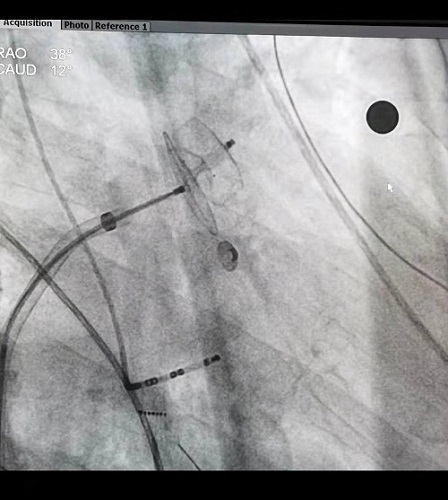

术中,张志辉教授带领罗文治主治医师及邓煦主治医师,首先对病人进行房颤的环肺静脉电隔离及左心房基质改良,随后应用心腔内超声,对患者的左心耳形态及直径大小进行了精确测量,结合X线下造影的影像,使用了ACP20mm的左心耳封堵器对患者左心耳进行封堵,封堵器到位顺利,一次性展开成形,再次应用腔内超声对展开后的封堵器进行测量,封堵器完美封堵左心耳开口,且对左心耳附近的结构没有影响,遂释放封堵器。整个手术过程患者均在清醒状态下,术中患者各项生命体征平稳。

装配左心耳封堵器

X线下左心耳封堵器